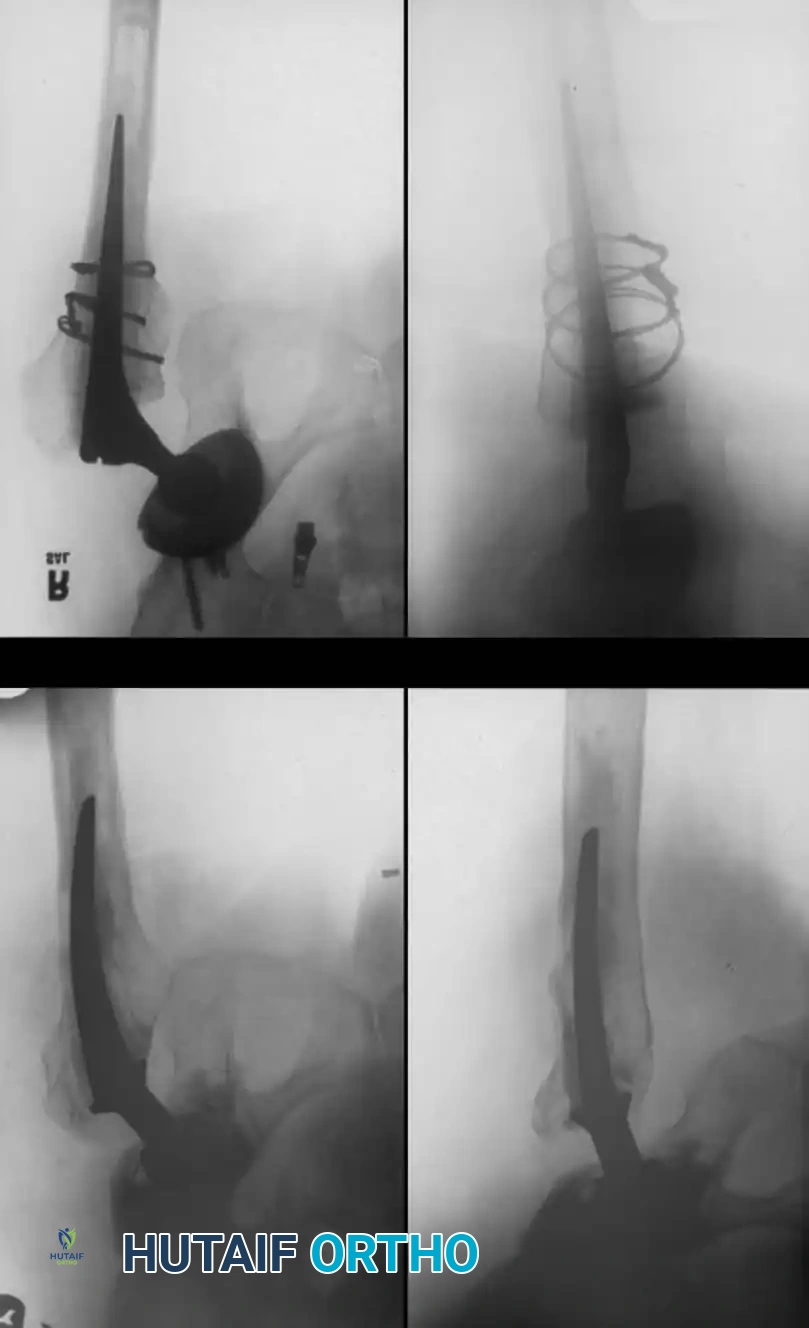

The Extended Trochanteric Osteotomy (ETO)

For complex femoral revisions, particularly those involving well-fixed cementless stems, varus remodeling, or extensive distal cement mantles, the Extended Trochanteric Osteotomy (ETO) is the gold standard.

Biomechanics of the ETO:

Unlike a standard trochanteric osteotomy, the ETO preserves the insertion of the gluteus medius and minimus proximally, and the origin of the vastus lateralis distally. This maintains a continuous myofascial sleeve, providing dynamic stability to the osteotomy fragment and dramatically improving union rates (typically >95%).

ETO Technique:

1. Measure the required length of the osteotomy preoperatively (usually 12-15 cm, ensuring it bypasses the well-fixed portion of the stem).

2. Elevate the vastus lateralis anteriorly to expose the lateral femur.

3. Use an oscillating saw or high-speed burr to make the posterior and anterior longitudinal cuts.

4. Complete the distal transverse cut, ensuring rounded corners to prevent stress risers.

5. Lever the fragment open anteriorly, hinging on the intact anterior periosteum and vastus lateralis.

Pitfall: When seating a diaphyseal-engaging stem, prophylactic cerclage cabling of the distal femur is highly recommended to prevent catastrophic intraoperative splitting of the diaphysis during final impaction.